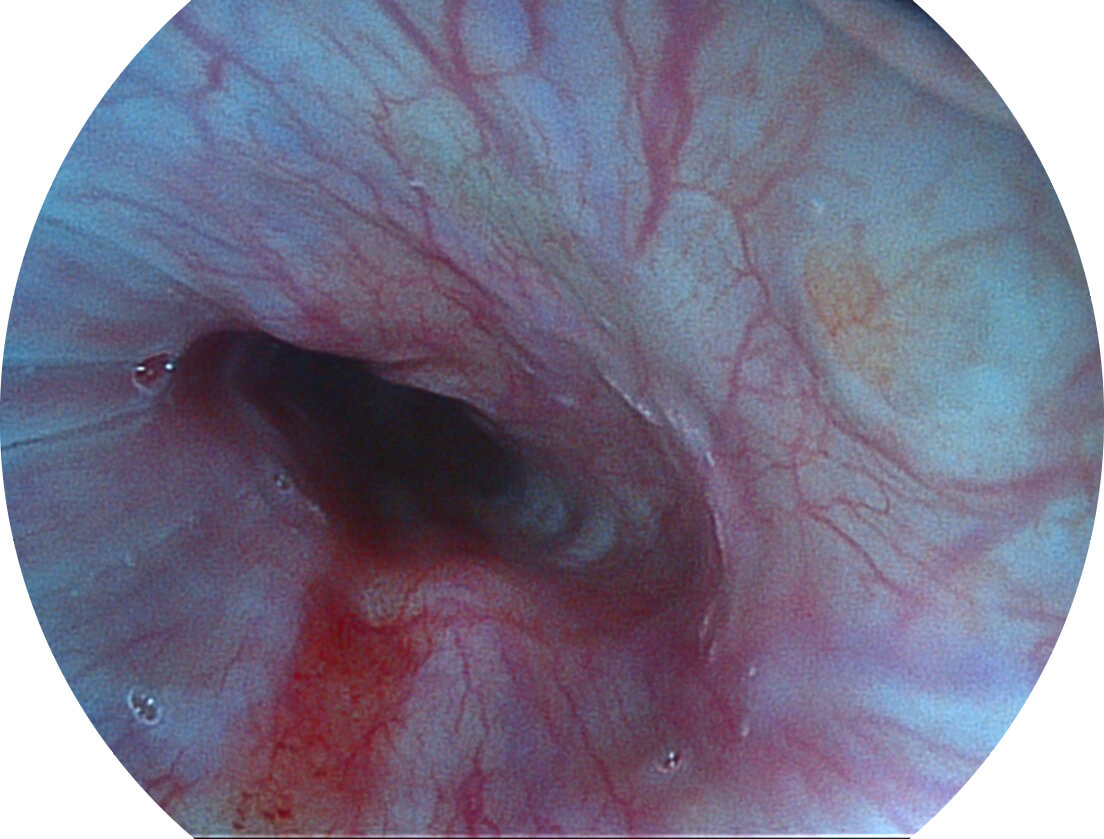

聚谱成像技术

Spectral Focused lmaging, SFI

图像具有高亮度、高黏膜血管颜色对比度的特点,且不改变粘液、食物残渣、粪便的基本颜色,可在中远景下进行观察,助力消化道早期疾病的诊断。

• 白光图像 SFI图像